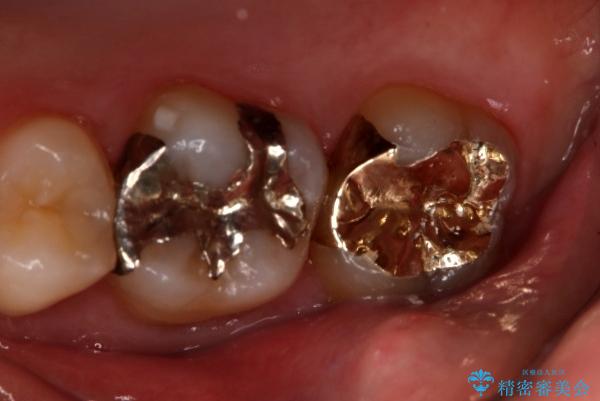

奥歯の再治療をしたい ゴールドインレー

- 右上大臼歯の再治療を希望され来院された患者様です。

切削量と形状を考慮し、インレーでの治療を計画しました。

患者様がゴールドを希望されたのでゴールドインレーを選択しました。

ゴールドは金属の中でも硬すぎず破折すこともほとんどないため歯科の治療に適した材料と言われています。